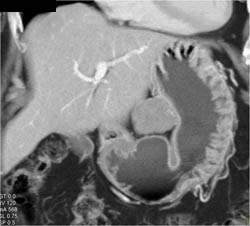

GIST Tumor